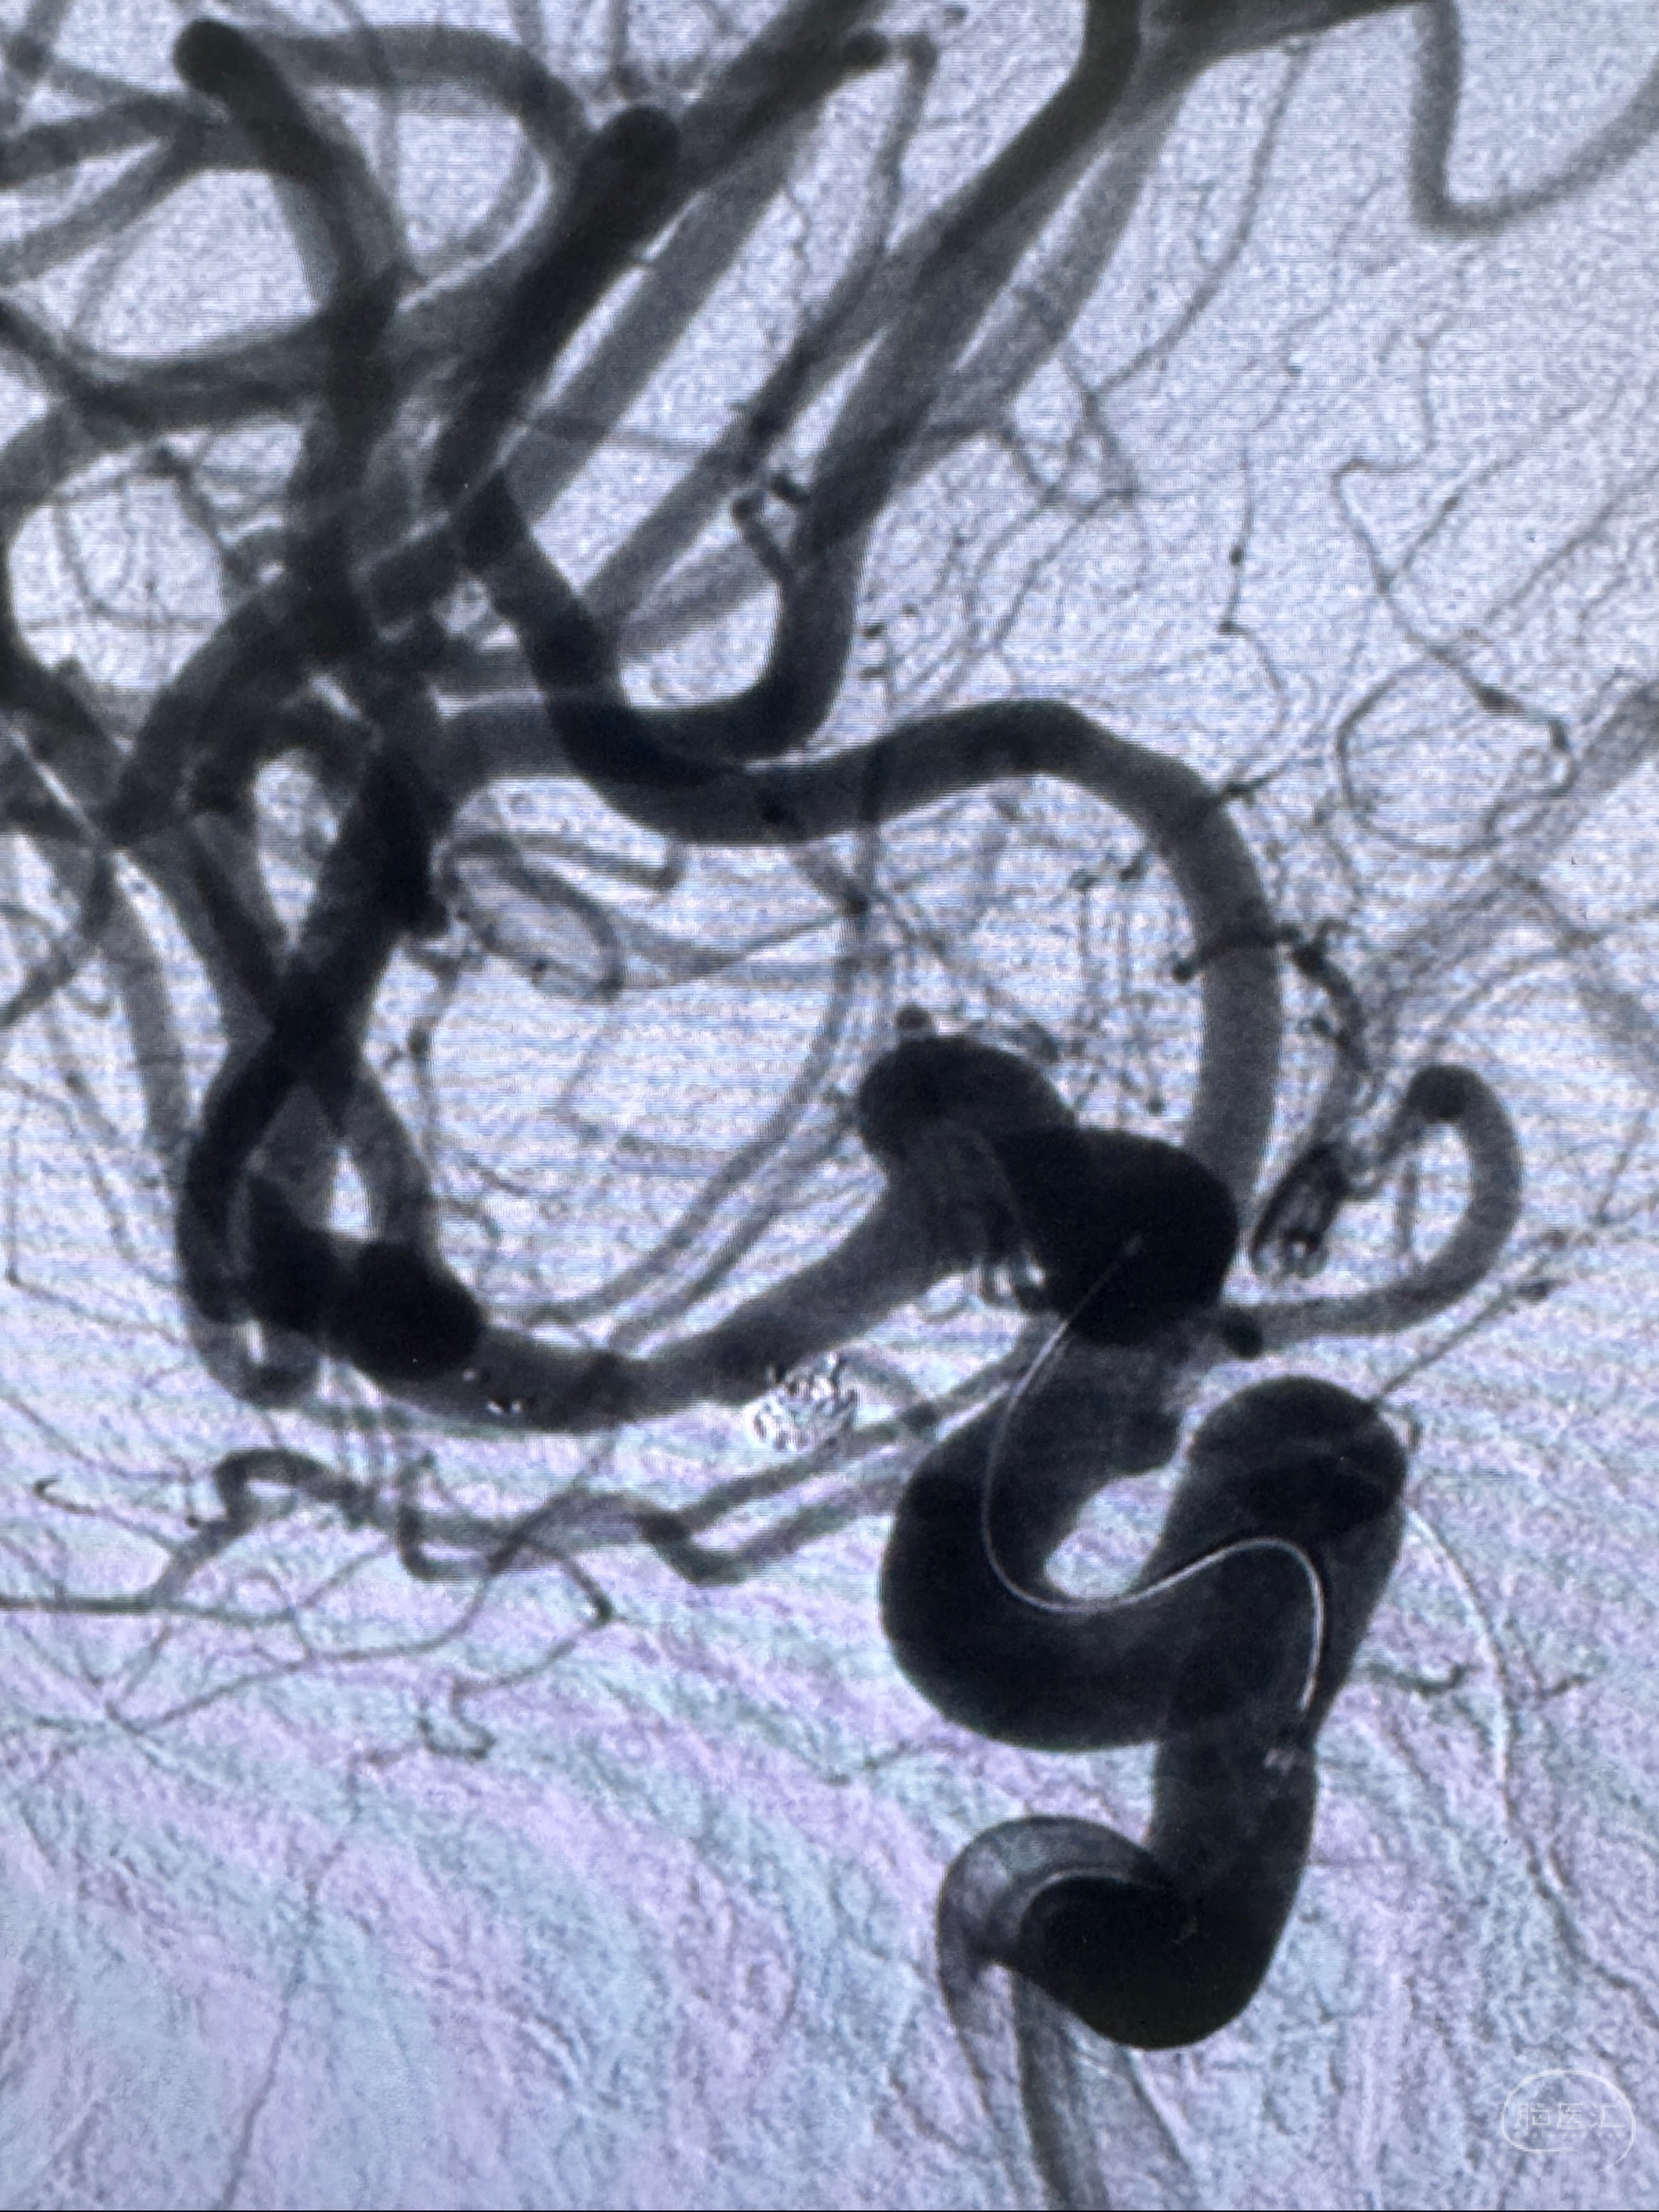

2023-11-24DSA:右侧大脑中动脉下干起始部动脉瘤,约2.3*2.5mm,形态规则

2023-12-04全麻下行支架辅助治疗

S-AB4-20mm